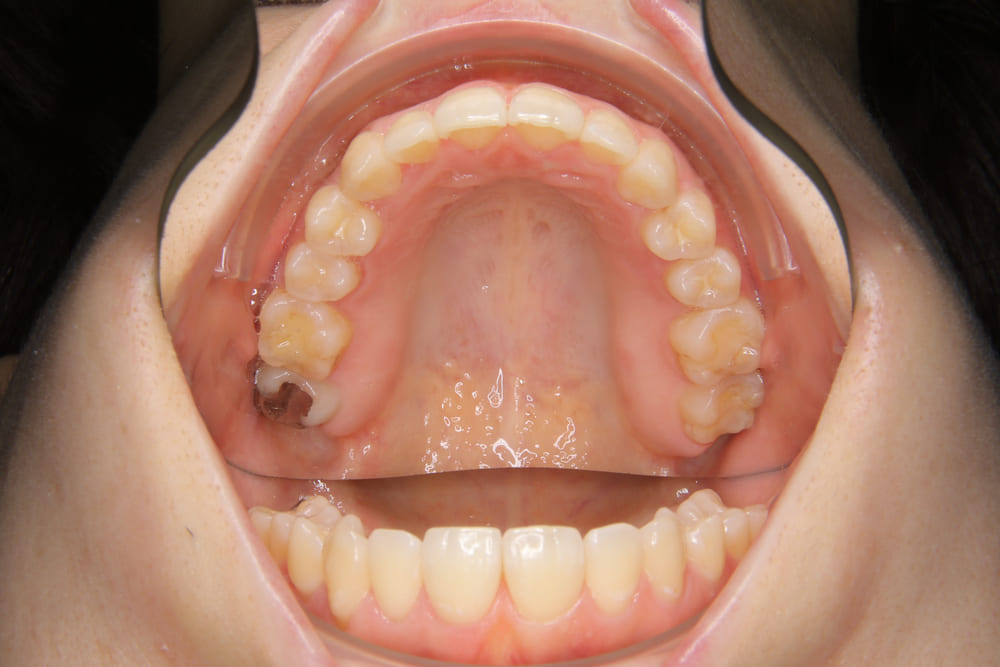

2精密検査

レントゲン撮影、口腔内写真・顔貌の写真撮影、口腔内スキャナー(iTeroなど)による精密な歯型採得など、治療計画の立案に必要なデータを収集します。